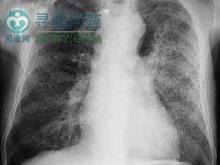

肺是尿毒症的最常见受累脏器之一,狭义的尿毒症肺炎是指尿毒症时,胸部X线片呈现以肺门为中心向两侧放射的对称型蝶翼状阴影,病变主要是肺水肿表现;广义的尿毒症肺炎是指尿毒症时呼吸系统出现的病理生理改变和临床表现,包括肺水肿、肺钙化,胸膜炎、肺梗死、肺纤维化和肺动脉高压。